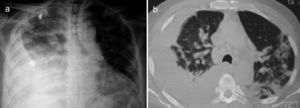

Un varón de 67 años de edad fue hospitalizado por disnea y fiebre de una semana de evolución. A su ingreso, el paciente se encontraba en malas condiciones generales y con una SatO2 del 78% respirando al medio ambiente. Sus signos vitales fueron FR 29min, FC 112min, TA 145/85mmHg y una temperatura de 37°C. La exploración física reveló un síndrome de derrame pleural derecho y muy escasos estertores finos en el hemitórax izquierdo. La radiografía de tórax y tomografía computarizada demostraron opacidades alveolares bilaterales y corroboraron la presencia de un derrame pleural derecho (fig. 1). Por laboratorio solo se documentó una leucocitosis de 21.400células/μl, de las cuales 9.400células/μl correspondieron a linfocitos. No presentó elevación de azoados y el examen general de orina no evidenció sedimento ni proteinuria. En la toracocentesis, un líquido amarillo turbio se obtuvo con un pH7,0; proteínas 6g/dl; glucosa 22mg/dl; DHL 1,066U/l, escasos polimorfonucleares y sin presencia de bacterias en la tinción de Gram. El paciente fue tratado inicialmente como neumonía asociada a un derrame pleural complicado y un tubo pleural le fue insertado en el hemitórax derecho al tiempo que le fue iniciado moxifloxacino 400mg IV cada 24h y meropenem 1g IV cada 8h, posteriormente, dicho esquema fue sustituido por vancomicina 500mg IV cada 6h y piperacilina 4g/tazobactam 0,5 g IV cada 6h. Sin embargo, durante los siguientes días no se observó mejoría clínica ni radiológica, y el drenaje de líquido pleural persistió a pesar de dichos esquemas antimicrobianos. La baciloscopia, los cultivos de líquido pleural y de sangre resultaron negativos. Tras una larga estancia en el hospital el paciente presentó una dermatosis generalizada (fig. 2a), y en una biopsia de piel se documentó una vasculitis linfocítica (fig. 2c). Este escenario se atribuyó inicialmente a un efecto adverso de los antimicrobianos. El panel de la hepatitis viral B y C, VIH, VDRL, pANCA y cANCA fueron todos negativos. Fue solo después de un examen físico detallado que se encontraron algunas úlceras en el pene (fig. 2b), sin embargo, la prueba de patergia no fue concluyente. El caso se diagnosticó como una forma incompleta de la enfermedad de Behçet versus granulomatosis de Wegener ANCA-negativa, por lo que fue tratado con metilprednisolona 125mg IV cada 6h presentando una rápida mejoría en sus condiciones generales y respiratorias permitiendo la retirada exitosa del tubo torácico y su alta hospitalaria al poco tiempo de iniciado el tratamiento. Desafortunadamente, el paciente falleció a las semanas siguientes debido a un cuadro de hemorragia alveolar difusa.